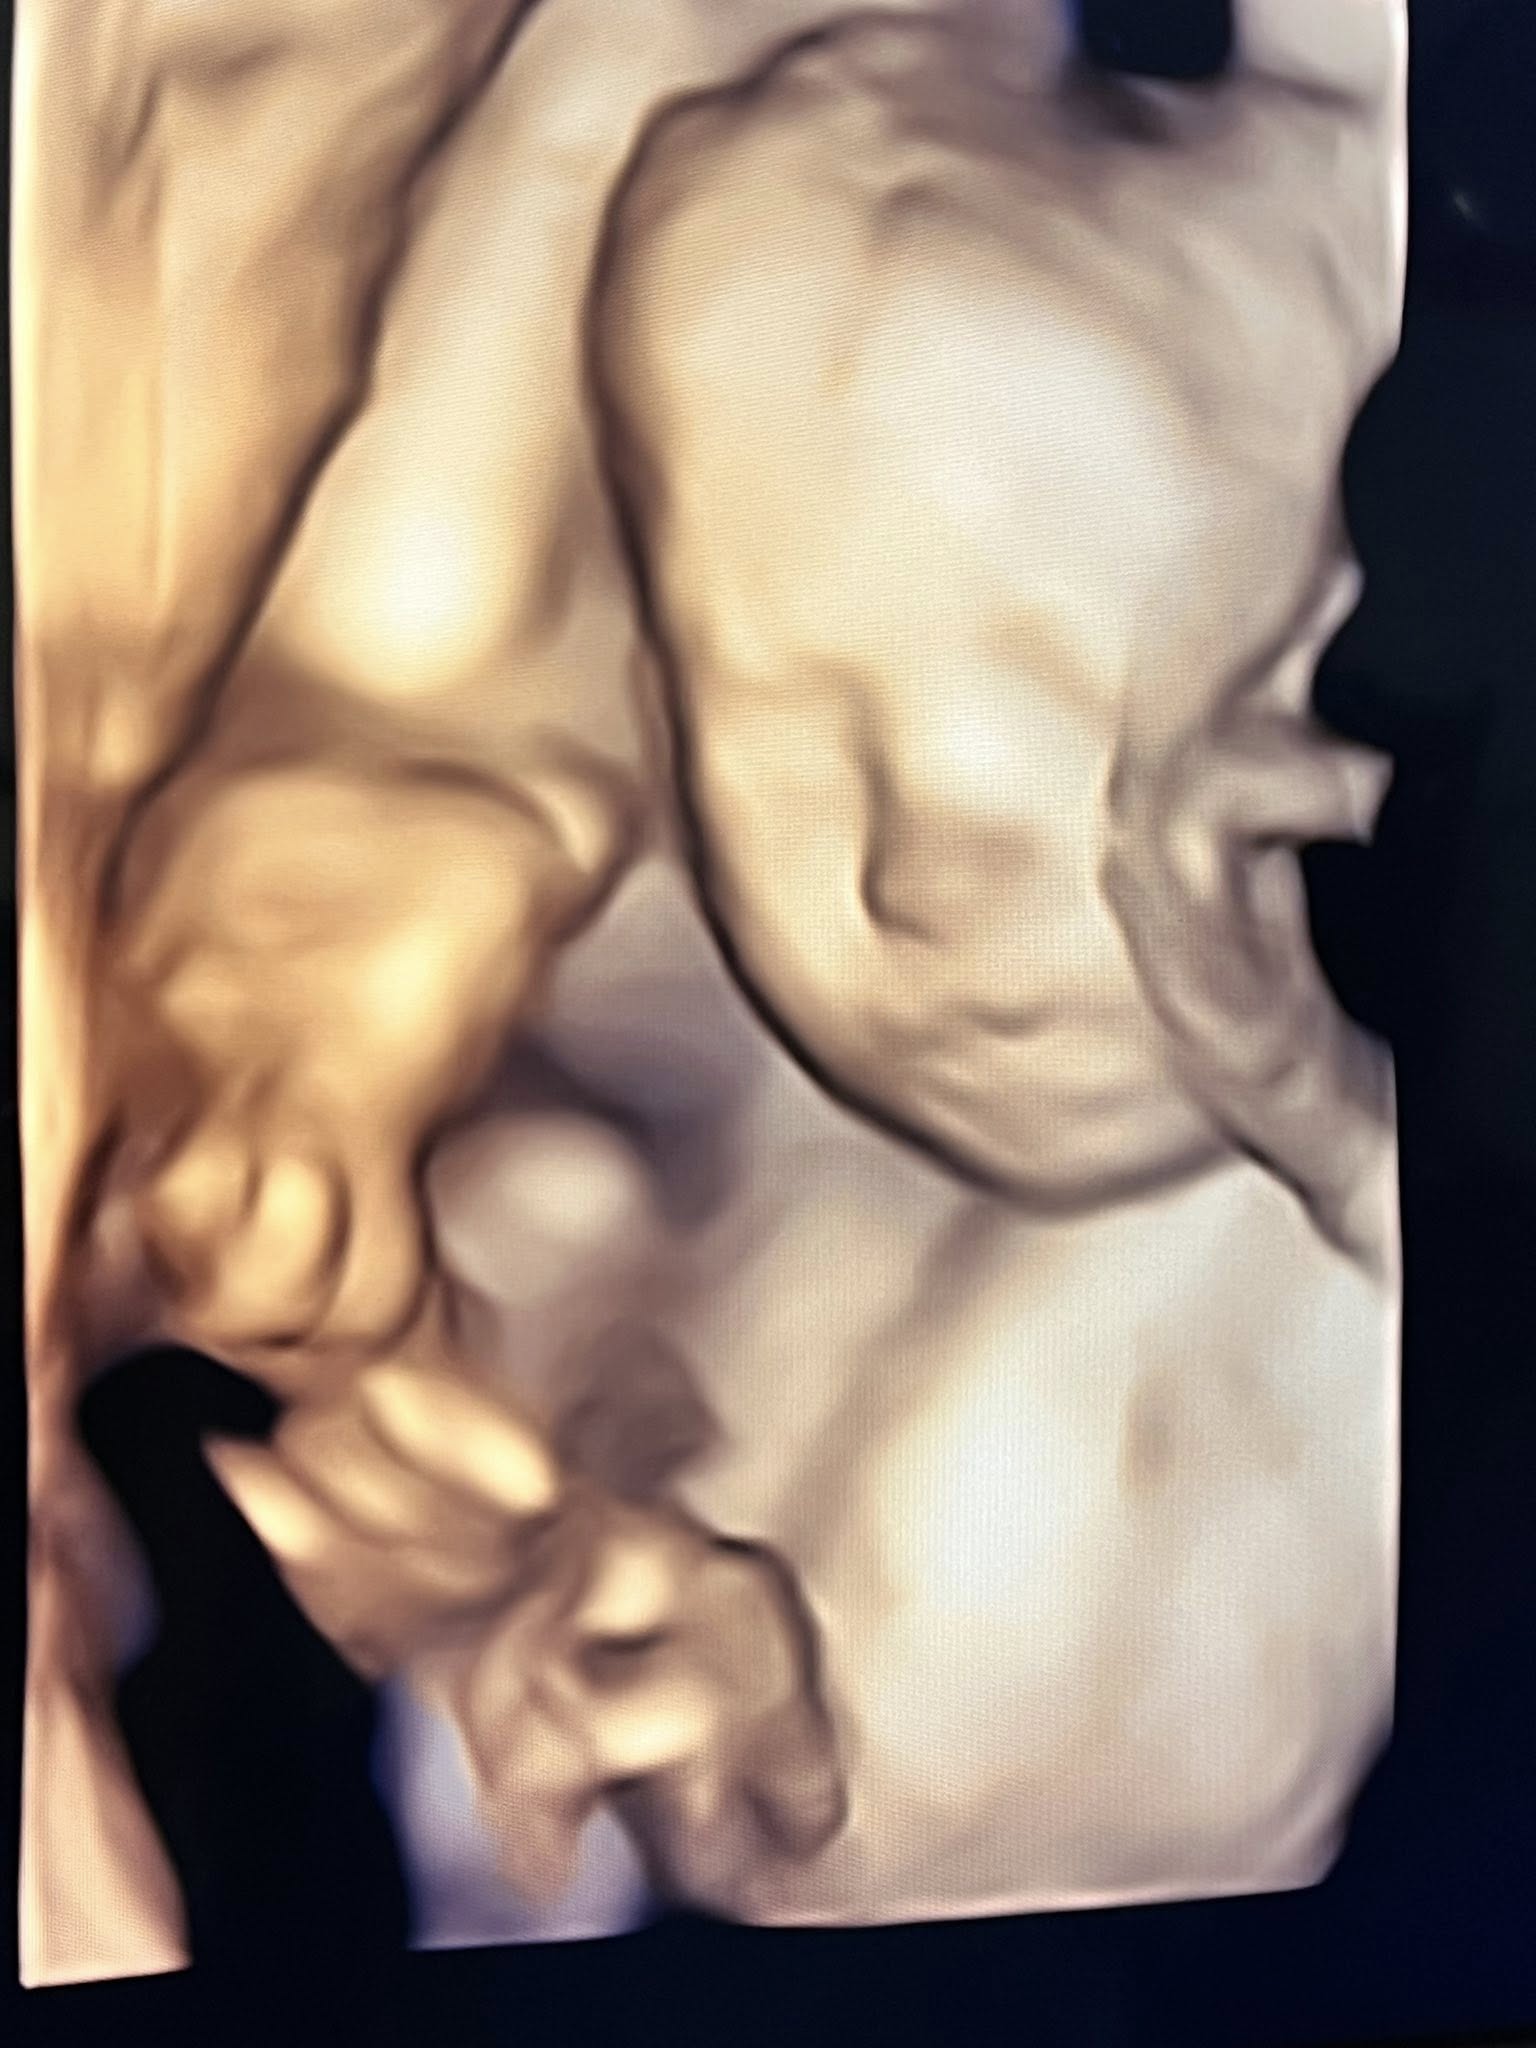

ทำเอาแฟน ๆ เตรียมสมัครเป็นพี่เลี้ยงออนไลน์กันล่วงหน้า เมื่อ เจมส์ เรืองศักดิ์ ลอยชูศักดิ์ ออกมาแชร์โมเมนต์อบอุ่น อัปเดตการตั้งครรภ์ของภรรยาคนสวย ครูก้อย นัชชา ลอยชูศักดิ์ พร้อมเผยภาพอัลตราซาวด์ของลูกสาวคนที่ 2 “น้องมีเมตตา” ที่ตอนนี้อายุครรภ์ครบ 6 เดือนแล้ว

จากภาพอัลตราซาวด์เผยให้เห็นเค้าโครงใบหน้าของน้องมีเมตตาอย่างชัดเจน นอนยิ้มหวานละมุน แถมจมูกโด่งสะดุดตา เรียกได้ว่าน่ารักน่าชังตั้งแต่อยู่ในท้อง โดยพ่อเจมส์เขียนแคปชันด้วยความเอ็นดูว่า “แม่หนูมีเมตตาของฉัน จมูกโด่ง ยิ้มหวาน” พร้อมอัปเดตว่า คุณหมอกล้วย แพทย์ผู้ดูแลครรภ์ครูก้อย ยืนยันว่าลูกน้อยแข็งแรงสมบูรณ์ พัฒนาการเป็นไปตามเกณฑ์ทุกด้าน ก่อนจะปิดท้ายด้วยมุกขำ ๆ สไตล์คุณพ่อว่า “สินค้าเด็กเข้าได้เลยครับ ( ฮาาา.... )” ทำเอาแฟน ๆ เข้ามากดไลก์และคอมเมนต์ชื่นชมความน่ารักของน้องมีเมตตาอย่างล้นหลาม

ด้านคุณแม่คนสวย ครูก้อย นัชชา ก็ไม่น้อยหน้า โพสต์คลิปอัลตราซาวด์ของลูกสาวเช่นกัน พร้อมแคปชันสั้น ๆ ว่า “แม่ว่า…ดูทรงยาว ทรงคมนะ” งานนี้หลายคนอดเดาไม่ได้ว่า น้องมีเมตตาน่าจะได้ความสูงยาวและเค้าโครงคม ๆ มาจากพ่อเจมส์และแม่ก้อยแบบเต็ม ๆ